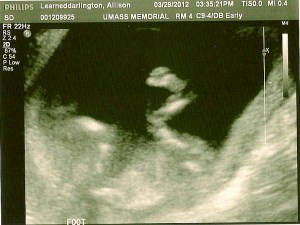

Here are a few of the images (head to the left side of the image, feet to the right side) the wonderful ultrasound technician gave us, she was great, constantly saying “oh, how cute!” But she probably says that with them all, huh? But we’ll pretend ours was extra cute!

Below is my favorite image, if you look close you can see little hands by the face and the legs are crossed with a little foot showing! The second image is one of the feet kicking and you can see the little toes! I say soccer player, Eric says hiker…